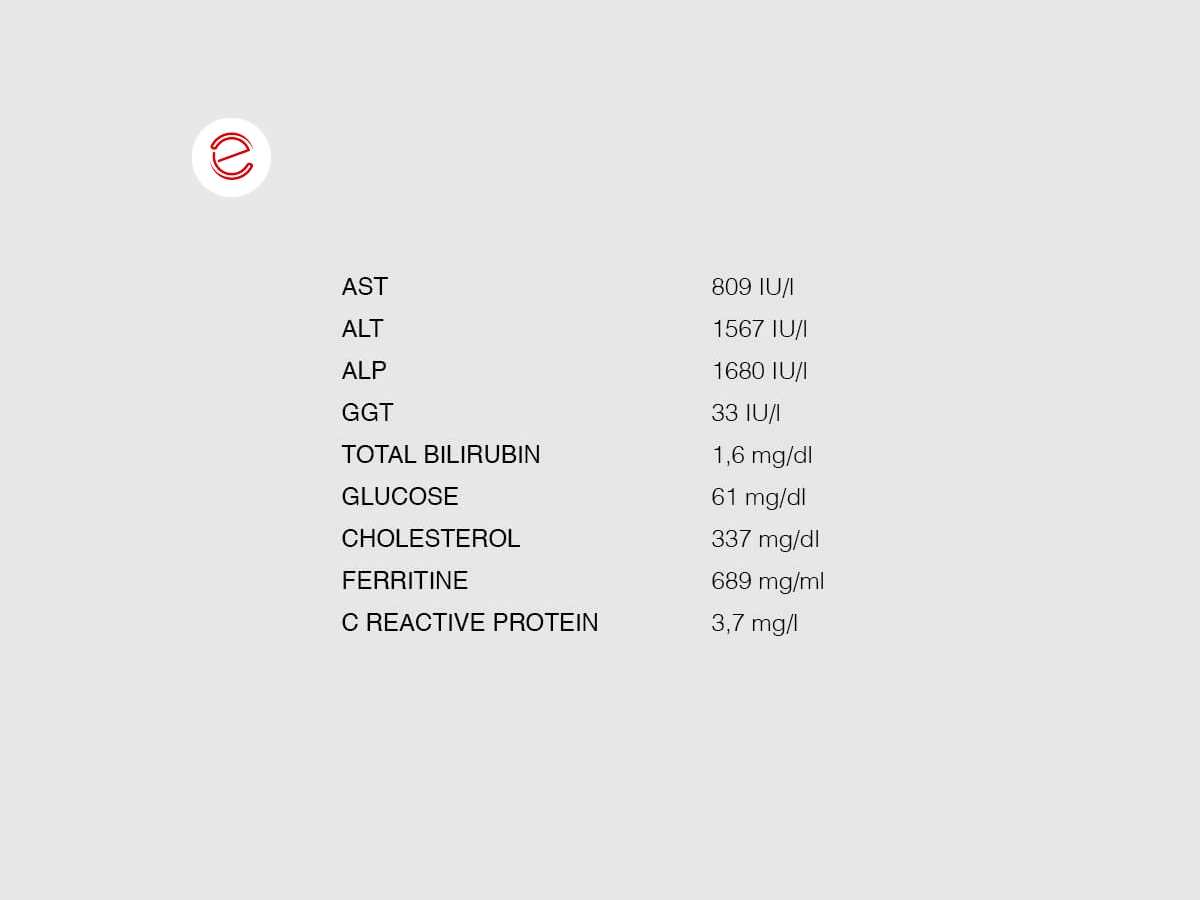

Diagnostica

Sono stati eseguiti esami delle feci per flottazione, che hanno dato risultati negativi. Il test della Giardia ha prodotto un risultato negativo. L’immagine mostra il risultato dell'esame ematobiochimico. L'emogramma è nella norma e non presenta note di rilievo.